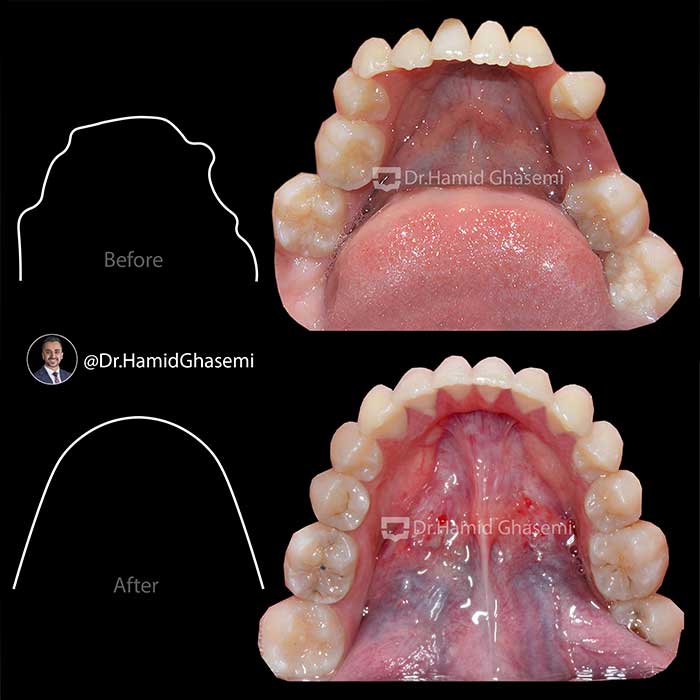

درمان ارتودنسی بدون کشیدن دندان در دختر خانم ۱۵ ساله با مشکل نهفتگی دندان نیش بالا و انحراف میدلاین دندانی در مدت ۲۲ ماه انجام شد.

Non extraction orthodontic treatment of 15 years old girl with impacted upper canine and upper dental midline deviation done within 22 months.